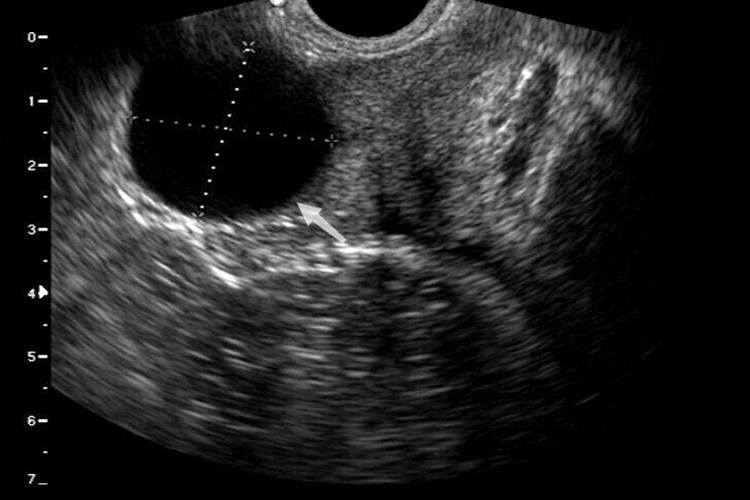

精囊腺囊肿超声的特征为囊肿形态呈圆形或椭圆形,内部为无回声区,合并出血时可见点状回声漂浮。囊肿多位于一侧精囊腺,常占据精囊腺的大部分或全部区域。囊壁多数菲薄,少数可薄厚不均。也可见多房性精囊腺囊肿。囊肿后方回声增强。